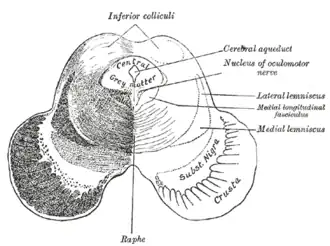

Вокруг водопровода располагается центральное серое вещество, в котором заложены ретикулярная формация, ядра III и ядра IV пар черепных нервов и др. На сечениях среднего мозга сильвиев водопровод может иметь вид треугольника, ромба или эллипса. Через него происходит циркуляция ликвора (спинномозговой жидкости)[1][2].

У человека представляет собой канал длиной около 15 мм, соединяющий в головном мозгу полость третьего желудочка головного мозга с четвертым[1]. Дорсальную стенку образует пластинка четверохолмия среднего мозга, вентральную — покрышка ножек мозга. Образуется в онтогенезе из полости третьего мозгового пузыря[2].

Вокруг Сильвиева водопровода находится центральное серое вещество (substantia grisea centralis)[2], анатомически относящееся к покрышке среднего мозга. Это серое вещество направляет свои восходящие проекции в ядра шва и в голубое пятно, а также в соматосенсорные и висцеросенсорные ядра таламуса. Оно также имеет нисходящие проекции в спинной мозг. Восходящие нервные волокна спиноталамического пути, проводящие ощущения боли и температуры, на своём пути в таламус делают промежуточную «остановку» в околоводопроводном сером веществе. Эта часть спиноталамического пути называется спиномезэнцефалическим путём. В свою очередь, воспринимающие болевые и температурные ощущения ядра таламуса направляют свои нисходящие волокна обратной связи к спинному мозгу также через центральное серое вещество. В центральном сером веществе в области дна водопровода располагаются ядра двух пар черепных нервов. на уровне верхних холмиков четверохолмия среднего мозга, ближе к срединной линии залегает парное ядро глазодвигательного нерва (III пара черепных нервов). Вентральнее от него залегает добавочное ядро глазодвигательного нерва (n. oculomotorius accessorius) — ядро Якубовича (Ядро Эдингера-Вестфаля). Несколько выше и кпереди от ядра глазодвигательного нерва залегает одно из ядер ретикулярной формации — промежуточное ядро (nucleus interstitialis, ядро Кахаля)[2].

Поперечный разрез среднего мозга. Цифрой 2 показан водопровод мозга Поперечный разрез среднего мозга на уровне нижнего двухолмия.

Поперечный разрез среднего мозга на уровне нижнего двухолмия. Поперечный разрез среднего мозга на уровне верхнего двухолмия.